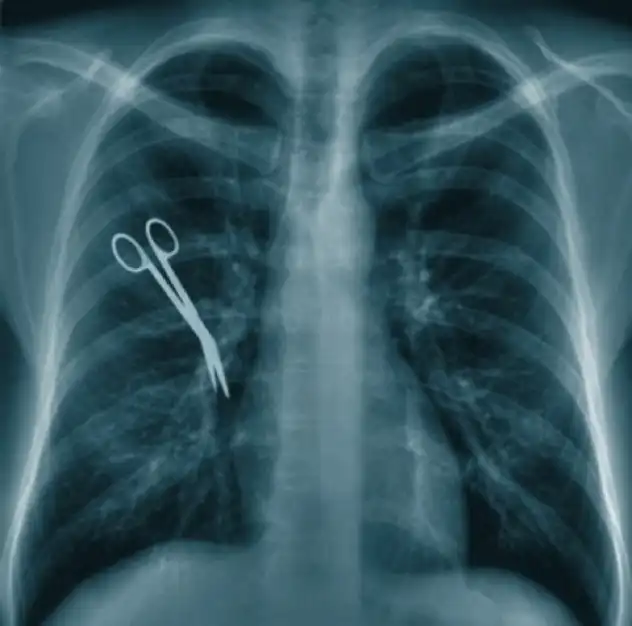

Дариуш Мазарей

Вполне вероятно, что многие слышали истории о людях, которым делали операции, а позднее обнаруживалось, что в их теле остались какие-то посторонние предметы. Подобные ситуации случаются полторы тысячи раз в год только в США. Это конечно не очень часто, но подобная ситуация может привести к серьезным внутренним травмам, инфекциям и сильной боли. В случае Дариуша Мазарея примечательно даже не то, что в его груди забыли 20-сантиметровый ретрактор и не то, что это было видно невооруженным взглядом после операции, а то, что потом, когда чуть позднее он обратился с жалобами на боль в груди в эту же больницу, ему посоветовали обратиться к психиатру. После месяца ужасной боли, многочисленных жалоб и утверждений врачей, что проблема только у него в голове, Мазарею все-таки сделали томографию и после этого удалили инородный предмет. Сейчас он судиться с этой больницей.